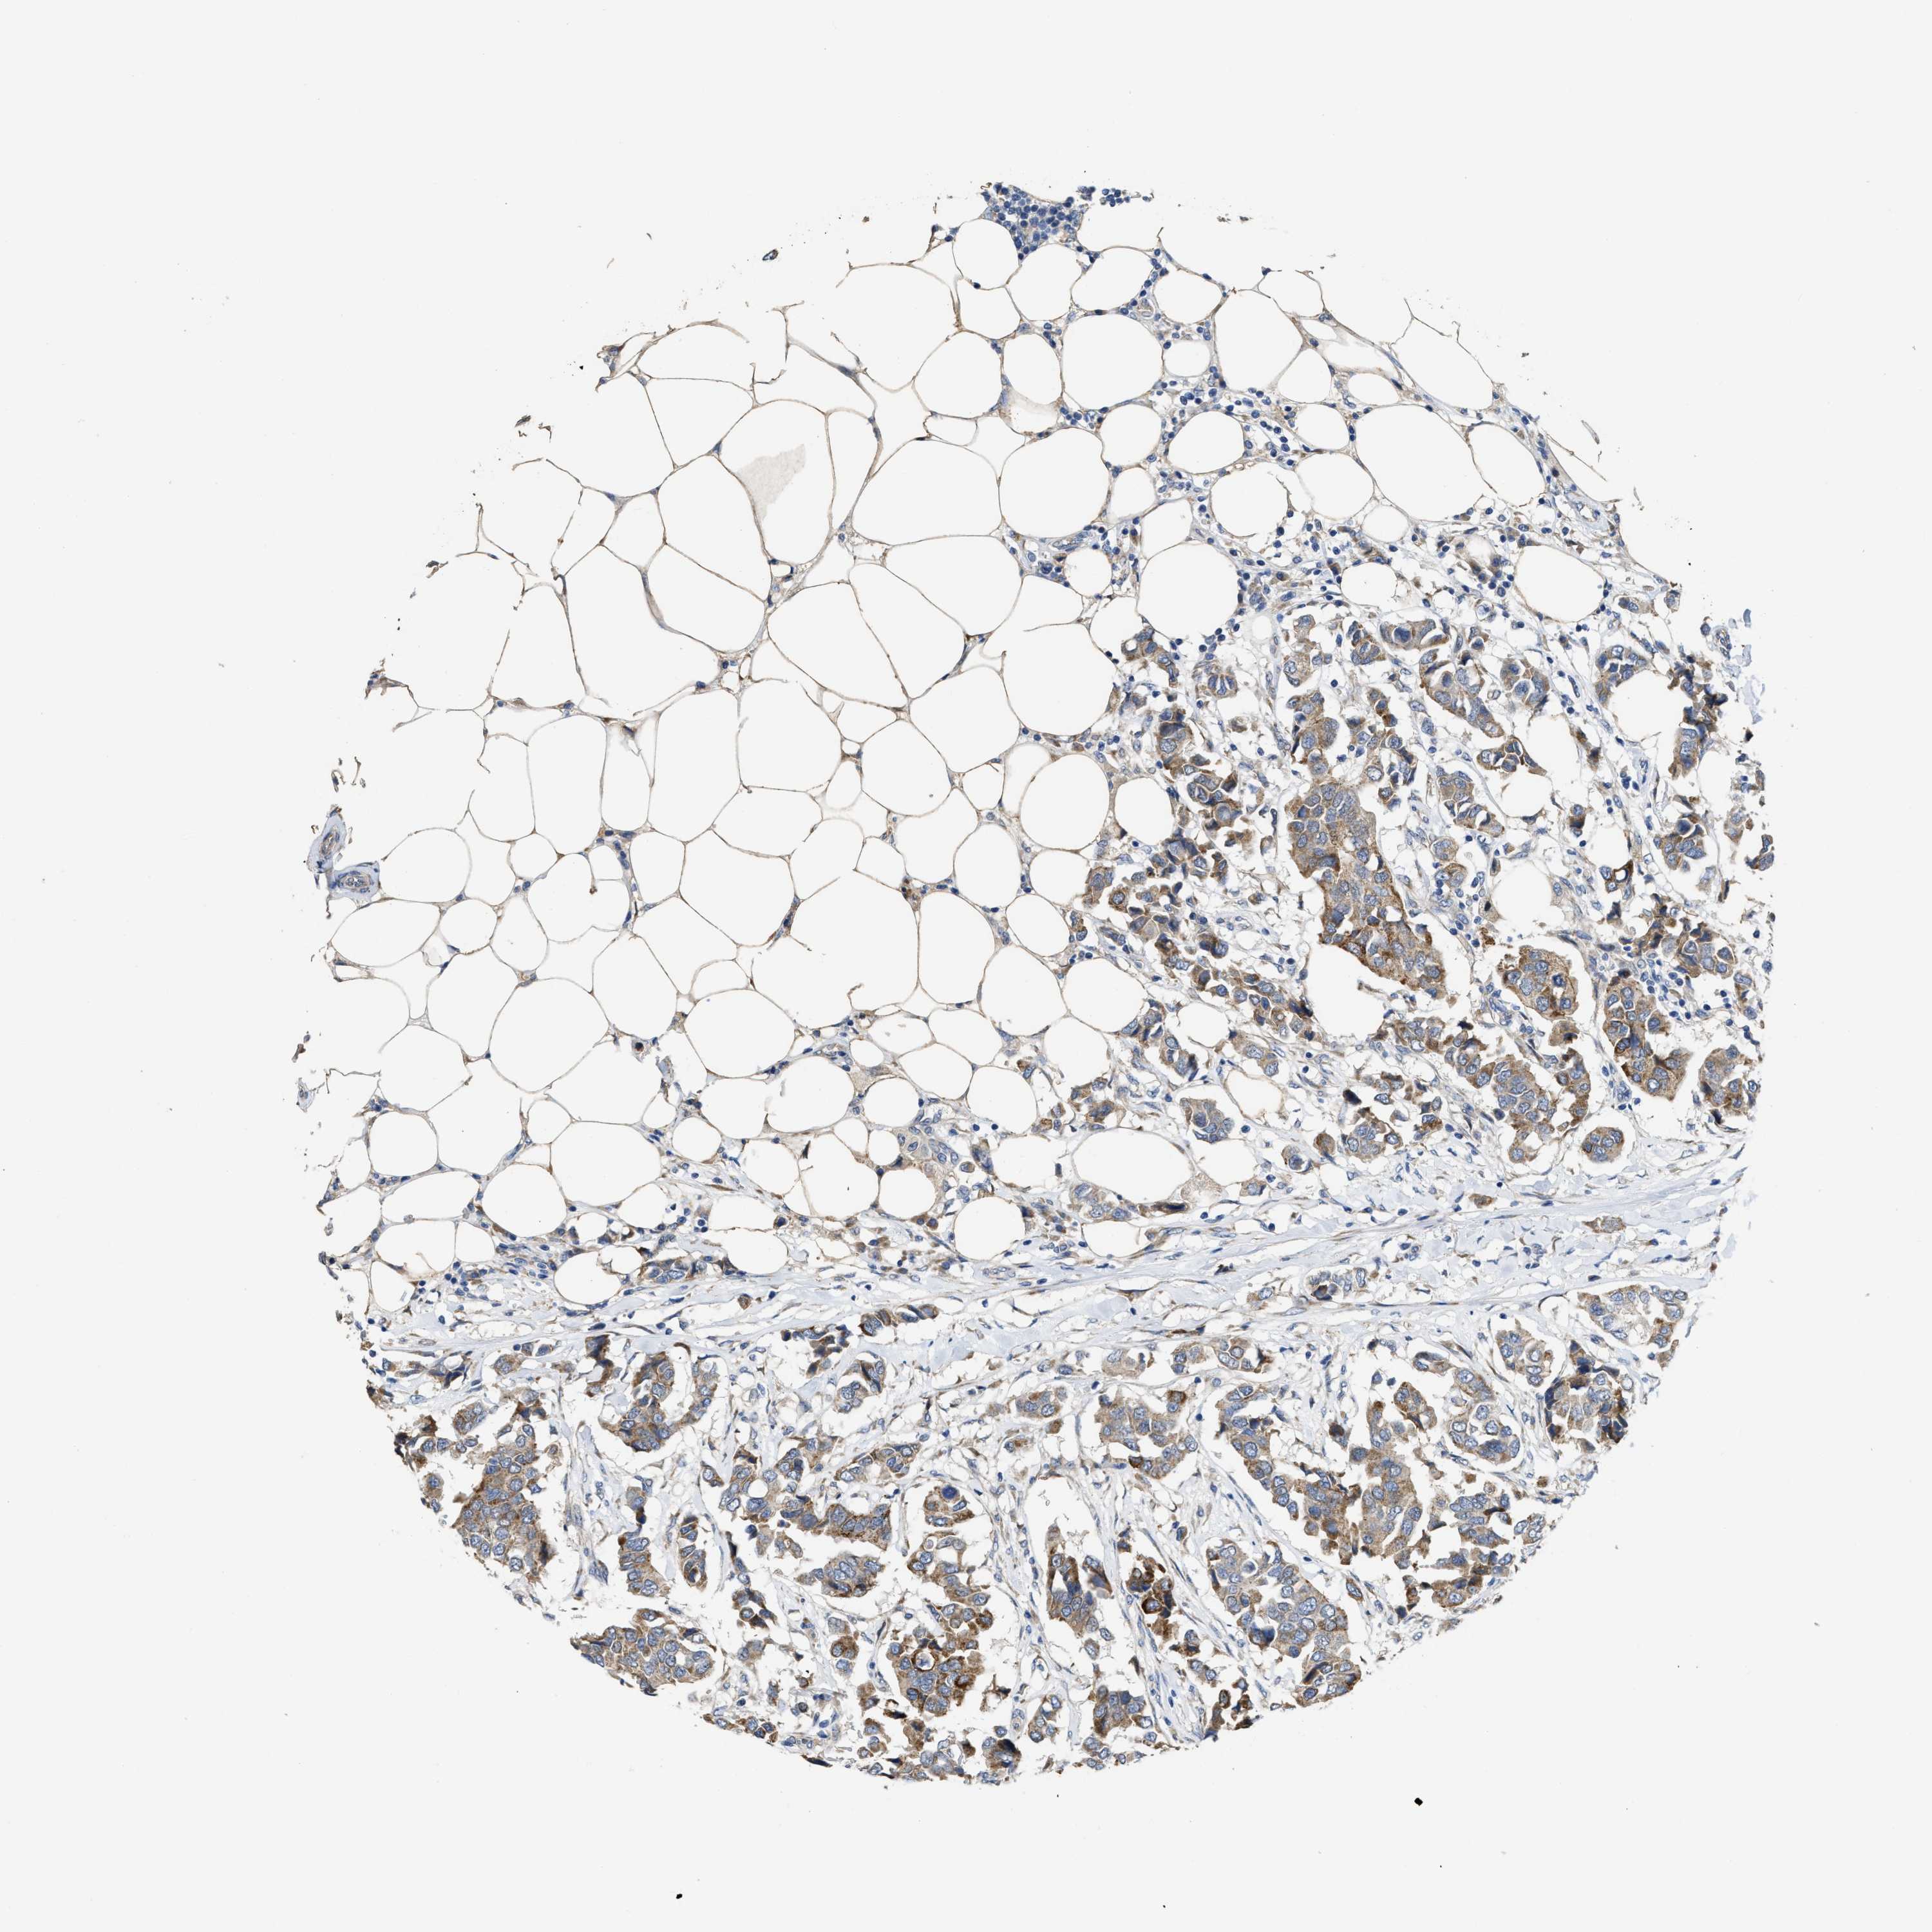

CANCER BREAST CANCER Show tissue menu

BRCA TCGA BRCA VALIDATION PROTEIN EXPRESSION